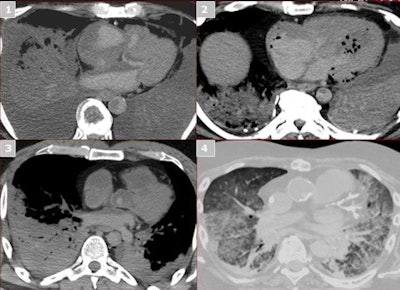

Postmortem images provide insight into the human body, which helps the autopsy team detect air within the body cavity; look for tiny lesions in areas hard to reach, such as bones; localize the lesions; and eventually plan the autopsy approach.

After the exam, CT images are transferred from the scanner to a life-sized touchscreen table (Anatomage, San Jose, CA) for display. This life-sized table is 3D-enabled, which allows manipulation of imaging data in multiplanar-reformation and volume-rendered modes.

Postmortem whole-body images are presented to the autopsy team members so they can visualize a 3D model of the case with lines, tubes, and instruments inside the body; find the visible abnormalities; and cut through the virtual body to localize the findings.

Although the findings of postmortem CT images are conveyed in a written report to the pathology team, radiologists are also physically present to interact with pathologists and point out lesions on the images to help provide better understanding of anatomical localization.